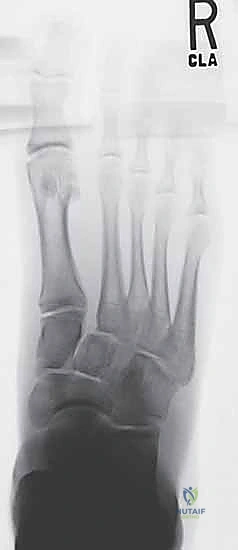

2. التصوير بالأشعة السينية (X-Rays) مع تحميل الوزن

الأشعة السينية العادية قد لا تظهر الإصابة إذا لم تكن العظام مزاحة بشكل كبير. السر يكمن في طلب أشعة سينية أثناء وقوف المريض وتحميل وزنه على القدم المصابة (Weight-bearing X-rays).

* يبحث الدكتور هطيف عن "علامة الفليك" (Fleck Sign)، وهي قطعة عظمية صغيرة مكسورة ومسحوبة من قاعدة المشط الثاني أو العظم المسماري الإنسي، وهي دليل قاطع على تمزق رباط ليزفرانك.

* كما يتم قياس المسافة بين قاعدة المشط الأول والمشط الثاني. أي اتساع يزيد عن 2 ملم يُعتبر غير طبيعي ويشير إلى عدم الاستقرار.